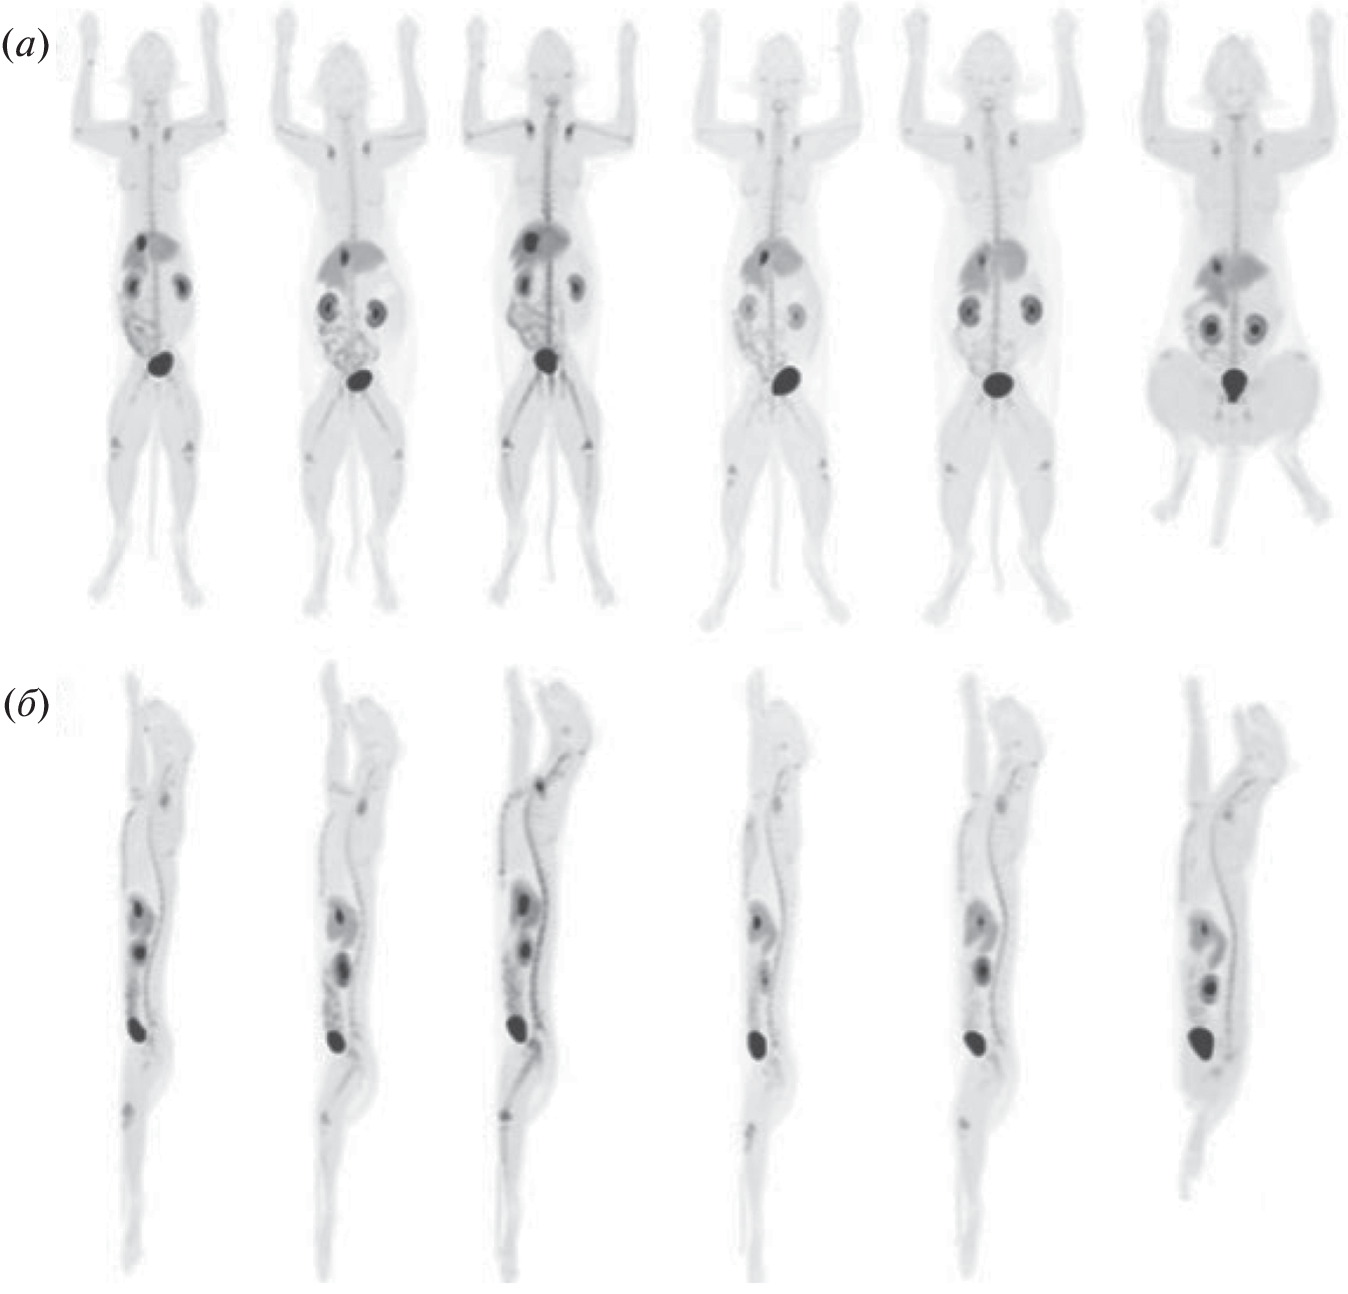

- Rowe J.A., Morandi F., Wall J.S., Akula M., Kennel S.J., Osborne D., Martin E.B., Galyon G.D., Long M.J., Stuckey A.C., LeBlanc A.K. // Veterinary Radiol. Ultrasound. 2013. V. 54. P. 299–306. https://doi.org/10.1111/vru.12024

- Reischl G., Dorow D.S., Cullinane C., Katsifis A., Roselt P., Binns D., Hicks R.J. // J. Nuclear Med. 2007. V. 43. P. 365.